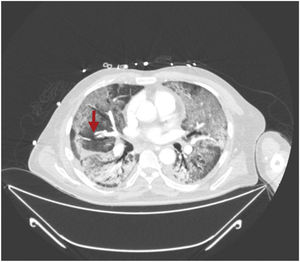

This is the case of a 64-year-old man with a past medical history of hypertension admitted to the ICU with a diagnosis of severe ARDS due to COVID-19-related bilateral pneumonia. The thoracic x-ray reveals a bilateral alveolar-interstitial pattern with damage to the right lung, especially the mid field (Fig. 1, pointer arrows). The blood test results show very high D-dimer levels (28970ng/mL) and due to suspected PTE, a thoracic echocardiography is performed that reveals the presence of RV pressure overload with positive McConnell sign. Following the echocardiographic findings, anticoagulant therapy with low-molecular weight heparin (enoxaparin 1mg/kg/every 12h) is initiated. A thoracic CCTA was performed for diagnostic confirmation purposes that revealed the presence of a repletion defect in the artery of the medial lobe lateral segment (arrows in Figs. 2 and 3) in the PTE setting. Also, the presence of diffuse bilateral damage and extensive areas of cobblestone pattern in a viral infectious process setting (Figs. 2 and 3). The patient remained on anticoagulant therapy until hospital discharge without any associated bleeding complications.